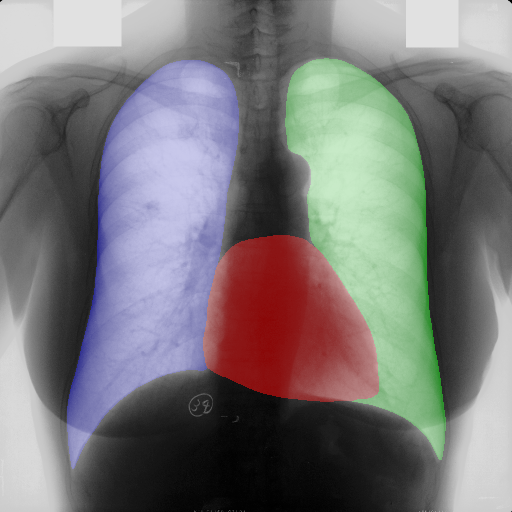

In this section, some examples of images and corresponding segmentations, generated with the approaches described in Section 3, are qualitatively examined. We also report some comments from three physicians on the generated segmentations, to provide a medical assessment of the quality of our method.

Figure 5 and Figure 6 display some examples — randomly chosen from all the generated images — of the label–maps and the corresponding chest X–ray images generated with the three methods described in Section 3, using the FULL_DATASET and the TINY_DATASET, respectively. We can observe that, with the single and two–stage methods, the images tend to be more similar to those belonging to the training set. For example, in most of the generated images there are white rectangles, which resemble those present in the training images, used to cover the names of both the patient and the hospital. Instead, the three–stage method does not produce such artifacts, suggesting that it is less prone to overfitting.